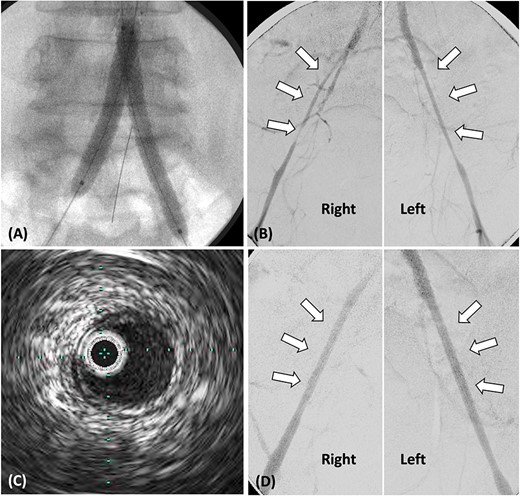

(A) Stent grafts placed from the abdominal aorta to bilateral CIA using the kissing stent technique. (B). Stenosis observed in both EIA, treated with plain balloon angioplasty only. (C) Post-balloon dilatation intravascular ultrasound reveals the absence of calcification or atheroma in both EIA. (D) Angiography post-balloon dilation reveals no EIA stenosis and calcification or atheroma.

Following stent-graft placement, angiography revealed severe EIA stenosis and delayed blood flow (Fig. 2B). Both EIA lengths were carefully dilated using a 5.0 × 100 mm SHIDEN HP balloon. After balloon dilatation, delayed blood flow resolved. Intravascular ultrasound (IVUS) finding post-balloon dilatation confirmed the absence of calcification or atheroma in both EIA, suggesting that EIA was pseudo-stenosis and no additional stents were inserted (Fig. 2C and D).